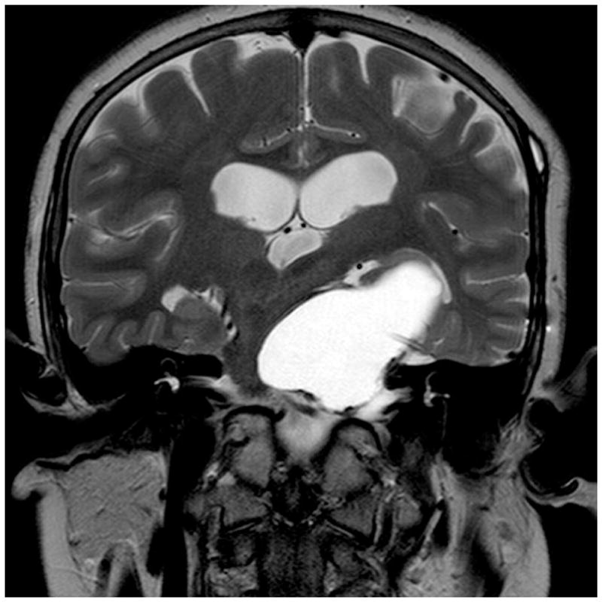

囊性颅咽管瘤用Ommaya储液囊保守治疗,上图为置入Ommaya储液囊之前

囊性颅咽管瘤用Ommaya储液囊保守治疗,上图为置入Ommaya储液囊之后以及反复拍打之后,囊肿大小明显减少